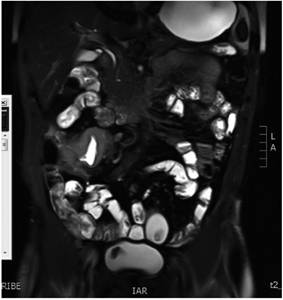

Se solicitó enterografía por RMN (entero-RMN) en la que se encontró un marcado engrosamiento concéntrico, asimétrico e irregular de la submucosa de la pared de íleon distal con extensión a la válvula ileocecal. Se estimó el grosor de la pared de 1,4 cm y la extensión longitudinal de 7 cm; también se encontró edema submucoso, restricción de difusión y realce poscontraste uniforme por cambios inflamatorios activos, estriación de grasa mesentérica (signo del cepillo), pequeñas adenopatías subcentimétricas no necróticas (hallazgos en relación con la actividad de EC, sin fibrosis) (Figura 2). Los estudios de tamizaje de infecciones resultaron negativos.